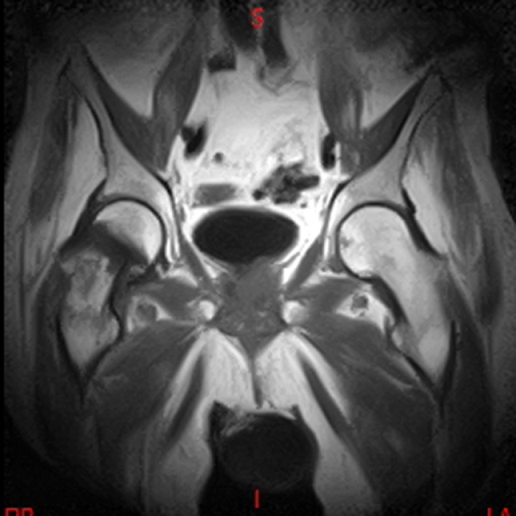

• RESONANCIA NORMAL CADERAS T2 CORONAL

• RESONANCIA NORMAL CADERAS T1 CORONAL